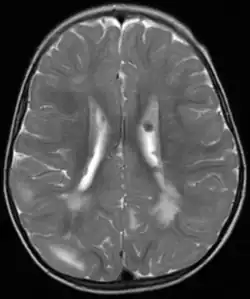

Fehlbildungen und Tumoren des Gehirns

Fehlbildungen und Tumoren des Gehirns werden oft frühzeitig festgestellt. Kortikale glioneuronale Hamartome, die so genannten Tubera (Vorwölbungen) im Bereich der Hirnrinde, gehen häufig mit Epilepsie einher und können kognitive Beeinträchtigungen verursachen, während subependymalen Riesenzellastrozytome und subependymale Knötchen aufgrund ihrer Nähe zum Ventrikelsystem typischerweise zur Entwicklung eines Hydrozephalus führen.